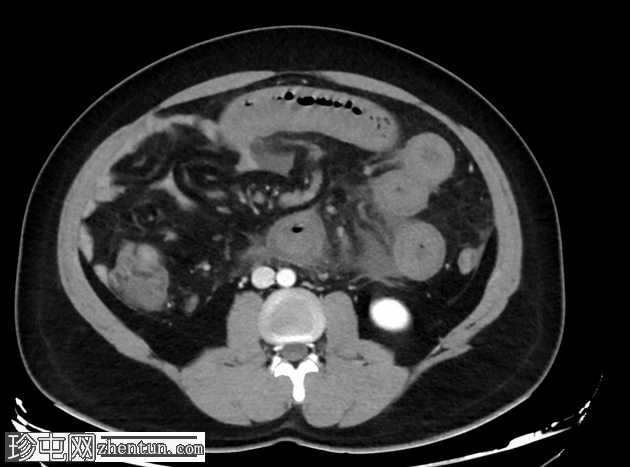

轴向C+门静脉期

肠系膜上静脉及其主要支流广泛血栓形成,延伸至脾静脉和门静脉,包括门静脉右支和近端左支。

小肠管增厚、水肿、低灌注,提示小肠缺血。

由于门静脉右支血栓形成,肝右叶低灌注,导致短暂性肝密度差(THAD)。

胃部膨胀,充满液体。

腹部少量游离液体。